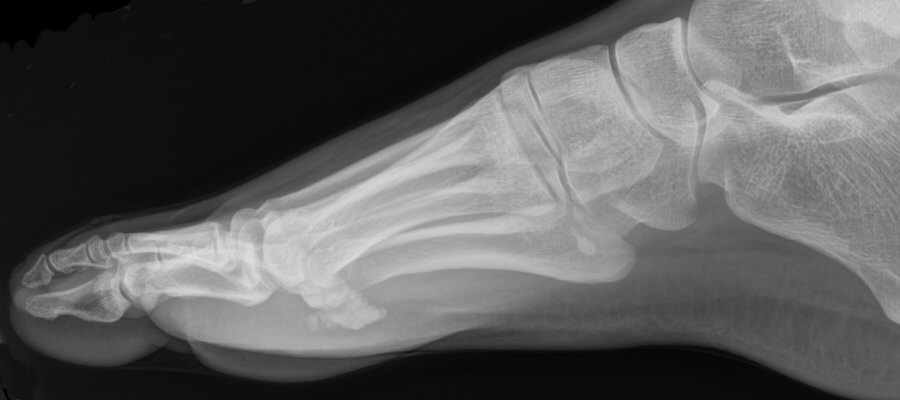

- Slätröntgen, frontal- och sidobild.

Exempel på bipartit lateralt sesamben